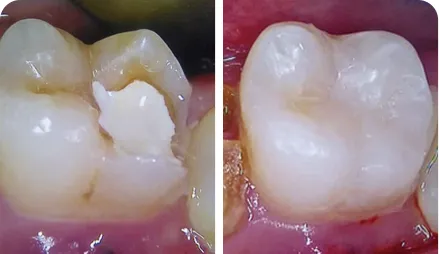

Direct Class II Composite Restoration of Endodontically Treated Tooth #36

Direct Class II Composite Restoration of Endodontically Treated Tooth #36